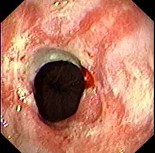

(单选题)胃镜检查如下图,诊断首先考虑()。

A:食管癌

B:贲门失迟缓症

C:幽门梗阻

D:反流性食管炎并食管狭窄

E:Barrett食管